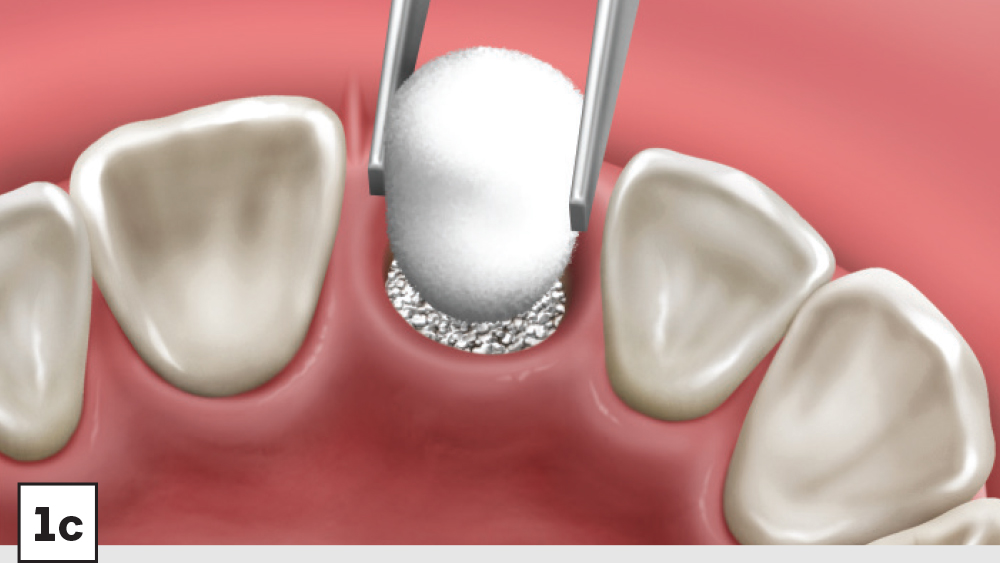

Five-Walled Socket Bone Grafting Technique (Figs. 1a–1d, 2a–2d)

1. Reflection: After extraction, a mucoperiosteal flap should not be reflected in most circumstances. However, a small subperiosteal pouch may be made around the margins of the extraction socket to allow for ease of membrane placement and suturing.

2. Preparation: The extraction socket should be free of soft-tissue remnants and bleeding should be present. If bleeding is not present, the remaining walls should be decorticated. Care should be exercised around adjacent teeth or vital structures. Bleeding from decortication will facilitate early vascularization and initiate the healing process.

3. Graft Material: The graft material (e.g., Newport Biologics Mineralized Cortico/Cancellous Allograft Blend) should be hydrated with sterile saline (0.9% sodium chloride) or platelet-rich fibrin (PRF) and then gently condensed into the socket. Small increments of material should be added into the socket, and a bone-packing instrument, such as the Bone Carrier and Spoon included with the 12-piece Newport Biologics Implant and Bone Grafting Instrument Kit (Glidewell Direct), should be utilized to condense the material to avoid air spaces (Fig. 3). Usually, when “push-back” of the material is present, the socket is packed sufficiently. Care should be exercised to avoid packing the graft material too densely, as this may interfere with angiogenesis and delay the healing process.

1. Membrane: A Newport Biologics Resorbable Collagen Plug should be cut in half and hydrated with 0.9% sodium chloride. The plug is compressed and placed over the socket, extending the collagen underneath the reflected subperiosteal pouch to increase retention.

2. Closure: Closure should be completed with a high-tensile suture material, such as polyglycolic acid (PGA) or PTFE, with a crisscross suture technique (Table 2). Care should be exercised to avoid suturing through the membrane. Gut sutures (plain, chromic) should be avoided, as they have a compromised tensile strength and will increase the probability of bone graft and membrane loss.